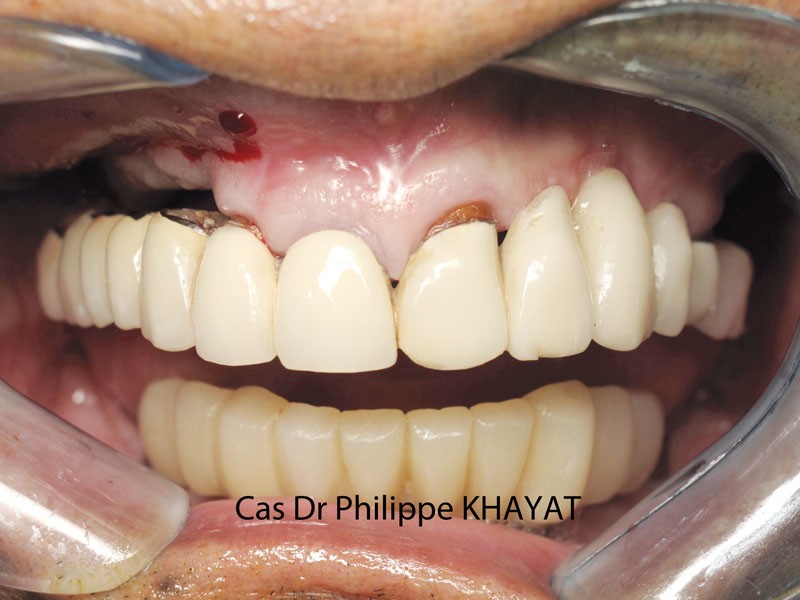

Philippe Khayat parlera de la « Mise en charge immédiate de l’arcade complète maxillaire » et il mettra l’accent sur les techniques qu’il a sélectionnées au terme de quatorze années d’expérience (fig. 1 à 4).